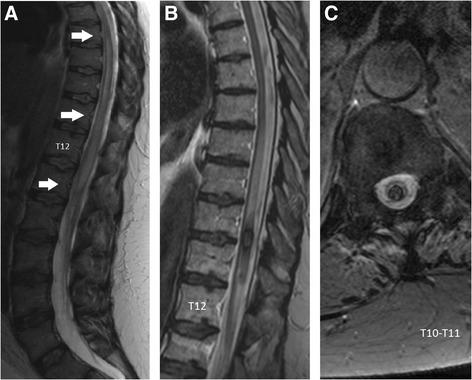

A 48-year-old Caucasian woman had relapsing neurosarcoidosis for 5 years, with inflammatory spinal and cerebral lesions. While on 20 mg corticosteroids, she experienced subacute paraparesia with right leg pain. A spine MRI revealed a low thoracic hematomyelia at the T10-T11 level. Despite high doses of corticosteroids, her condition continued to worsen. Surgical evacuation of the hematoma was performed 10 days after the onset of bleeding, and she partially recovered.

一名48岁的白种女性患有复发性神经结节病5年,有脊柱和脑部炎症性病变。在服用20毫克皮质类固醇期间,她出现亚急性下肢轻瘫并伴有右腿疼痛。脊柱磁共振成像显示在T10 - T11水平有胸段脊髓血肿。尽管使用了高剂量皮质类固醇,她的病情仍继续恶化。出血发作10天后进行了血肿手术清除,她部分康复。